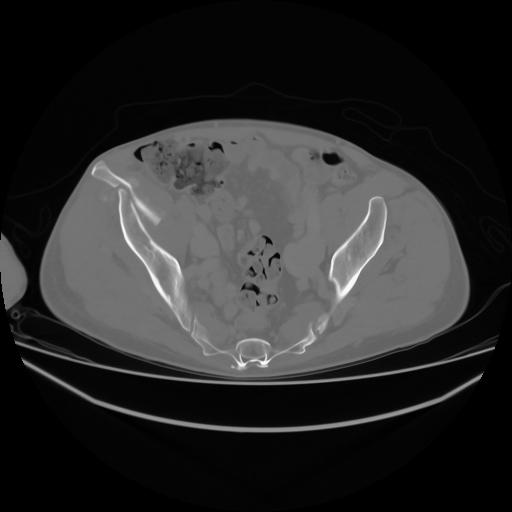

4 CUERPO,CE,Axial,3.0,CUERPO,,